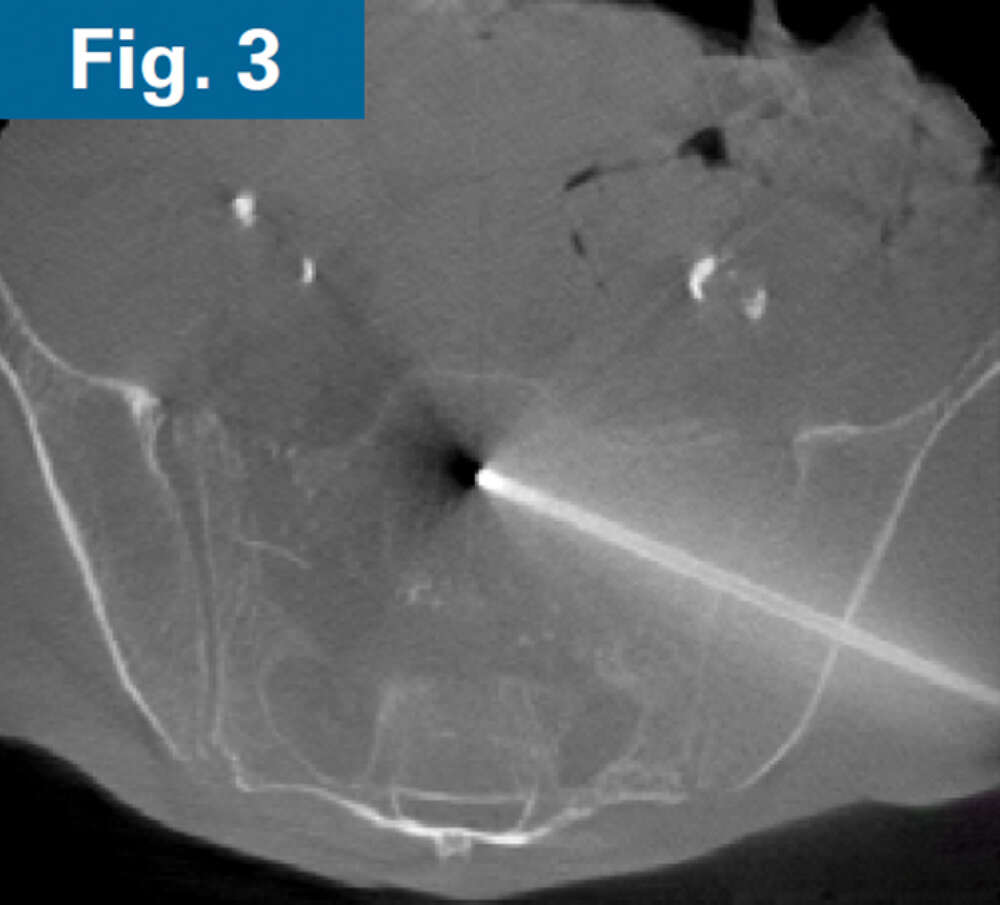

His pelvic abscesses were debrided and washed (lateral window) and antibiotic beads were placed followed by percutaneous placement of bilateral ilio-sacral style S1 implants. Intraoperative CT scan was performed after placement of 3.2 mm guidewires to confirm safe path of placement for iFuse TORQ implants in the setting of poor visualization of the foramen (Fig. 3). Bilateral 13.5mm iFuse TORQ implants were placed and the patient was allowed weightbearing as tolerated for activities of daily living at his home (Fig. 4).

Firoozabadi - spinopelvic dissociation - 4 Firoozabadi - spinopelvic dissociation - 4